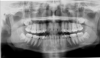

A physical assessment of the oral cavity and surrounding landmarks has three components: the extraoral assessment, the intraoral assessment, and radiographs. The extraoral assessment involves palpation of the submandibular and sublingual glands, cervical lymph nodes, pre- and post-auricular lymph nodes, TMJ, any asymmetries, lips, skin and facial structures, thyroid gland, and muscles of mastication. An intraoral assessment includes visualizing all landmarks in the oral cavity and gingival and buccal mucosa, along with the dentition. Radiographic assessments may involve a panoramic image (Figure 1) or cone-beam computed tomography (CBCT) as required, which must be read by someone trained to do so.

Fig 1. A radiographic assessment may include a panoramic image.

Figure 1